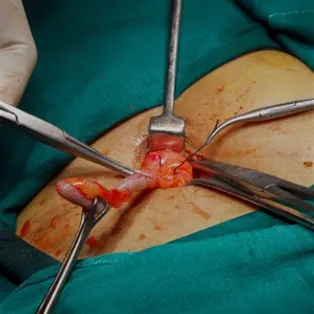

O tratamento da apendicite aguda é cirúrgico em quase todos os casos. Representa uma exceção o grupo de pacientes pediátricos (ou não) com diagnóstico tardio de plastrão inflamatório. Esses podem beneficiar-se de tratamento com antibióticos e apendicectomia eletiva. O procedimento cirúrgico para tratamento da apendicite depende do estágio da doença e caracteriza-se por remoção cirúrgica do apêndice, lavagem da cavidade, drenagem de coleções localizadas ou, nos raros casos de comprometimento grave do intestino, ressecção parcial do colo direito. Em qualquer fase da doença, a abordagem cirúrgica pode ser realizada por cirurgia convencional aberta (laparotomia) ou por cirurgia minimamente invasiva (videolaparoscopia), sendo esta a via de acesso mais utilizada atualmente. É realizada através de 2 ou 3 pequenas incisões, e com o auxílio de um monitor.

Figura 1: incisão abdominal em apendicectomia convencional aberta. Figua 2: posicionamento de trocateres em apendicectomia videolaparoscópica

A videolaparoscopia tem a vantagem de oferecer melhor avaliação do restante da cavidade abdominal no início do procedimento, podendo-se identificar outras causas de dor abdominal (diagnóstico diferencial), principalmente quando o quadro ainda pe duvidoso. Essa vantagem é potencialmente mais relevante em mulheres, nas quais a doença inflamatória pélvica (DIP) representa um diagnóstico diferencial muito freqüente e o tratamento é bem distinto. Outro grupo de pacientes que se beneficia bastante dessa abordagem são os candidatos à grandes incisões no abdome para que a cirurgia seja realizada com segurança, como é o caso de obesos e aqueles com suspeita de peritonite nas apendicites complicadas. A lavagem da cavidade peritoneal nas peritonites é totalmente factível pela videolaparoscopia. Em alguns casos inciais, a abordagem pode ser videoaassistida com a utilização de paenas 2 pequenas incisões da parede abdominal.

A apendicectomia laparoscópica necessita de menos tempo de internação hospitalar, é menos dolorida, a recuperação é mais rápida e apresenta menor índice de complicações do que a apendicectomia convencional, entre essas a taxa de infecção de ferida operatória, além do resultado estético melhor.